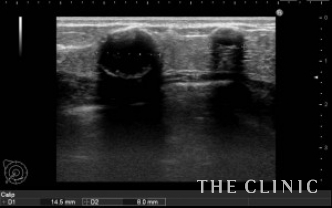

この方は、8年前に他院で脂肪による豊胸術を受けられました。その後、乳がん検診で多発する石灰化したしこりを指摘されたため、当院を受診されました。超音波検査では、右に7個、左に5個の石灰化したしこりを認めました。